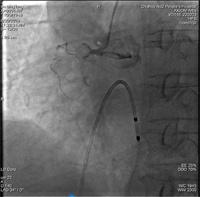

诊断急性下壁心梗,入院时已出现低血压休克症状。行冠状动脉造影提示右冠脉开口完全闭塞,导丝通过及普通球囊扩张后行血管内超声(IVUS)检查,提示近段及中段两次存在严重狭窄伴360°重度钙化,这些包绕血管的钙质就像禁锢在血管腔上的“盔甲”,使用常规球囊无法通过并扩张钙化部位,普通的球囊扩张处理只能是“以卵击石”。心血管内科吴义权副主任医师、孙春根主治医师、夏秋旺主治医师团队经全面评估后,决定给患者使用国内最新的冲击波球囊,采用血管内冲击波治疗。选择一枚3.0mm*12mm冲击波球囊分别送至右冠近段、中段钙化部位,总共发放5组冲击波,冲击波结束后,造影可见钙化部位狭窄明显减轻,经IVUS检查可见钙化环多处断裂,随后由远至近段串联植入3枚支架。整个手术过程中,患者无任何不适症状。